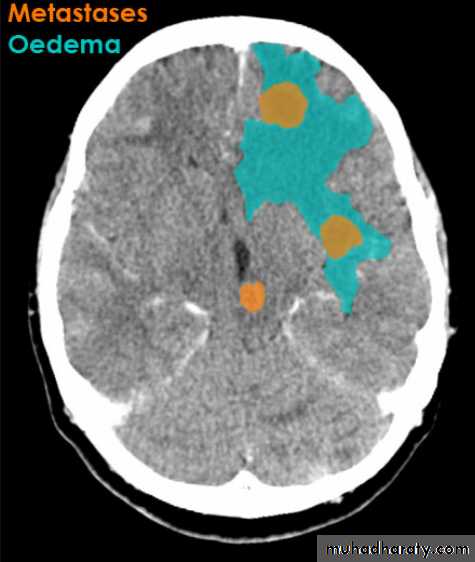

Secondary metastasis

Old age group above 50 Y , any lesion within the cerebellar hemisphere it is secondary metastasis unless proven otherwise F. from breast CA M. from bronchogenic CA .

Appear as nodular single or multiple lesion hypo dense or hyper dense .

Surrounded by per focal edema

Enhanced as solid or ring pattern of enhancement .

CT Scane